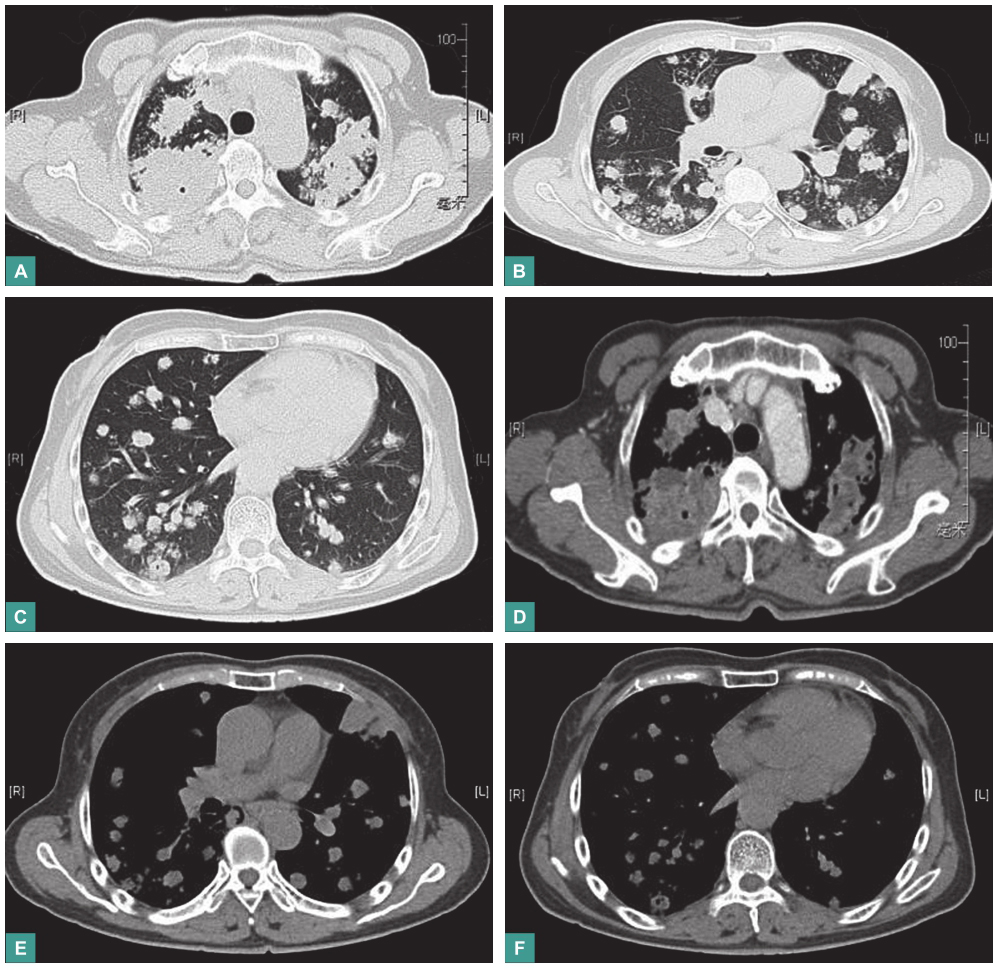

(4)影像学检查

胸部CT平扫和增强扫描示双肺弥漫多发结节及肿块,纵隔内气管前、腔静脉后部分淋巴结轻度增大(图1)。

图1 胸部CT表现

4.影像学检查

胸部CT显示双肺弥漫性多发结节和肿块,上肺部明显,局部病灶有小空洞,纵隔内淋巴结无明显肿大,增强扫描显示肺内病灶无明显强化。